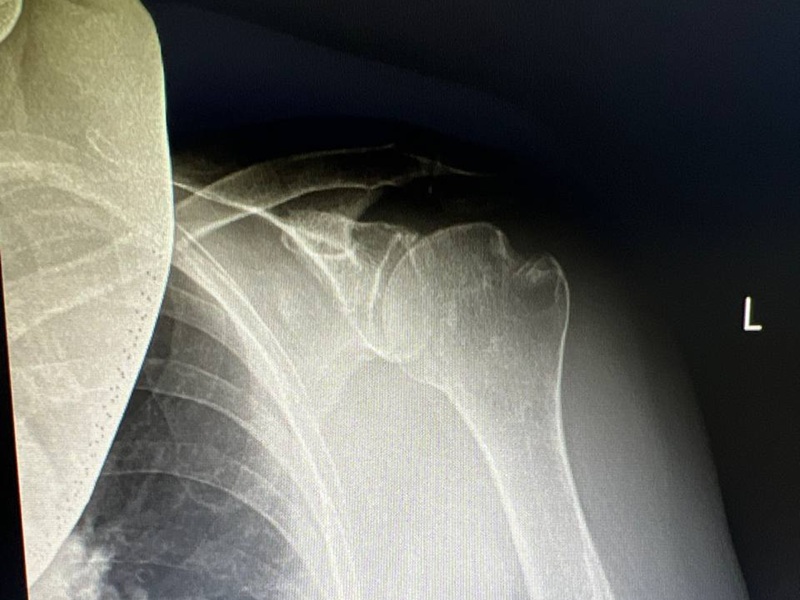

Пацієнту необхідно пройти дослідження (КТ, МРТ, рентгенографію), які забезпечують візуалізацію плечового суглоба, визначити його індивідуальні особливості, щоб підібрати протез потрібних розмірів та конфігурації. Отримані результати вплинуть і на вибір методу встановлення ендопротезу.